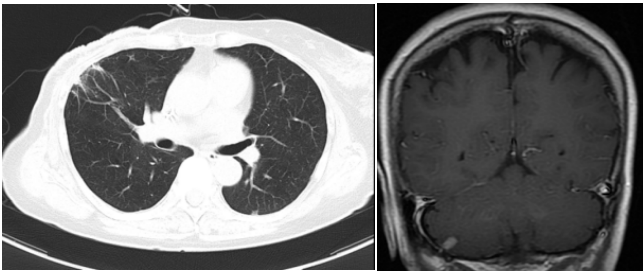

两个疗程后复查CT:右乳Ca伴右腋下淋巴结M(较前相仿),伴两肺弥漫性转移(图2,较前进展);肝实质异常密度影,考虑转移,较前相仿;胸腰椎转移灶,较前相仿。疗效评价PD。

图2. 2019.01两肺转移灶

两个疗程后复查CT:右乳Ca伴右腋下淋巴结M(较前相仿),伴两肺弥漫性转移(图3,较前缓解),肝脏转移灶消失(图3)。胸腰椎转移灶,较前相仿。疗效评价PR。

图3. 2019.03两肺转移灶(左图),肝左叶转移灶(右图)

④三线治疗:曲妥珠单抗(汉曲优) 300mg Q3W+吡咯替尼 320mg QD+唑来膦酸4mg Q3M,并予以局部区域放疗。维持治疗至2022.03.31出现新发左肺转移灶及右侧小脑转移灶。行支气管镜检查,并取左肺下叶背段支气管开口见新生物活检,病理提示:(左肺结节)乳腺癌转移,Ki-67(20%,+),ER(-),PR(-),HER2(3+)。右侧小脑异常信号,1.2cm(图5),考虑转移。疗效评价PD,PFS 16个月。

图5. 2022.03左肺及右侧小脑影像图